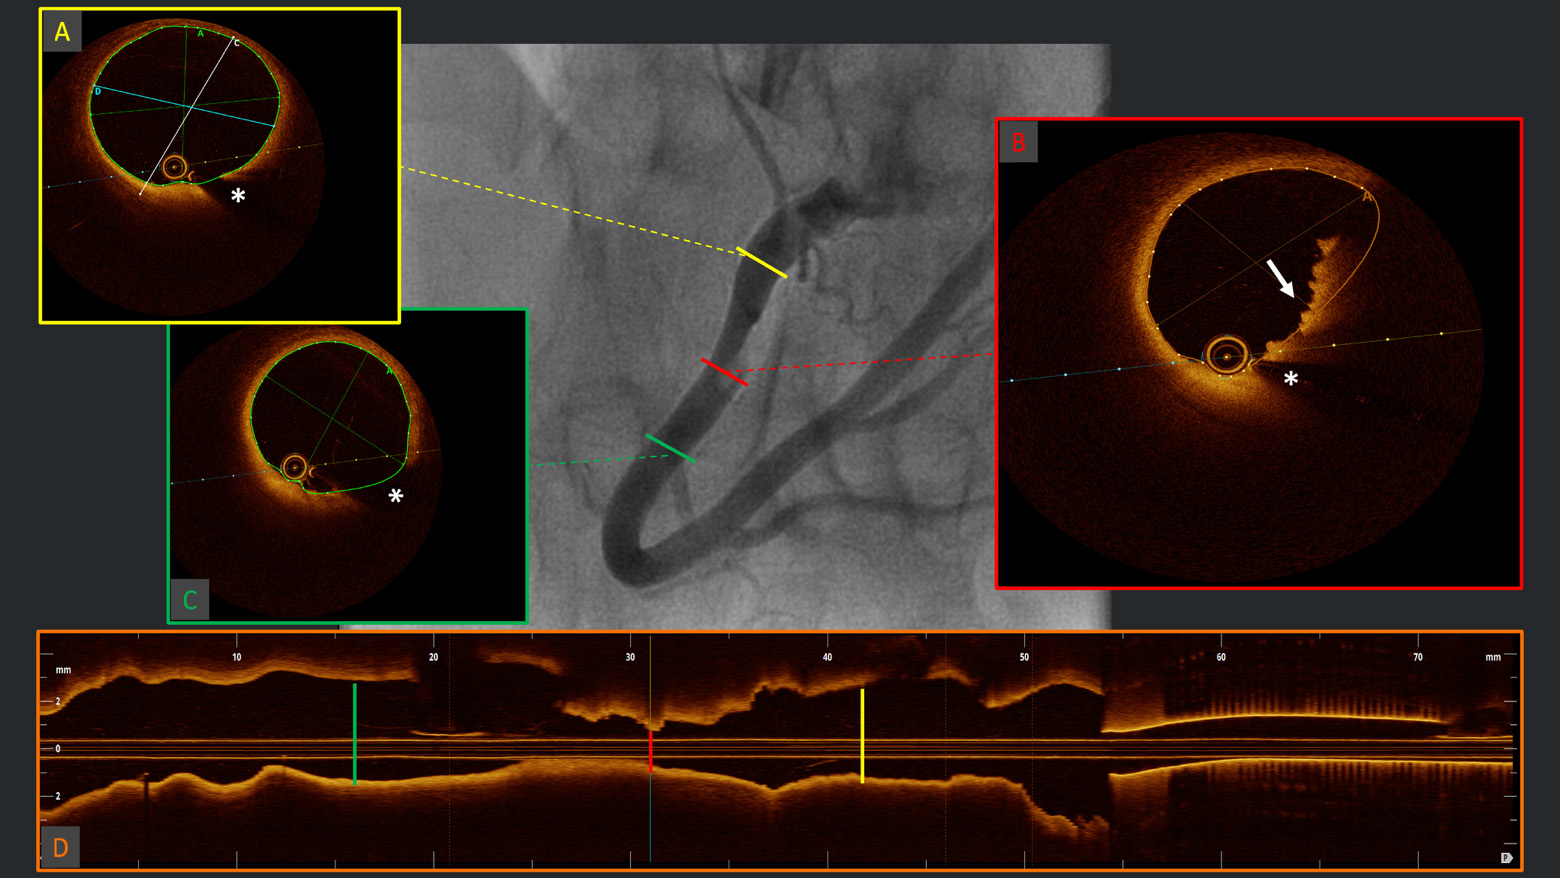

All the aforementioned systems represent significant advancements in the evolution of intravascular coronary imaging. An overview of the available main technical features and characteristics of these next-generation devices is presented in Table 3, along with examples of the respective screen interfaces in Fig. 4 (Ref. [83, 86]). Challenges such as high costs and the need for specialized training must be further addressed in the future to fully capture the potential of OCT and provide a comprehensive management of both primary and secondary prevention of CAD.

Fig. 4. Examples of the screen interfaces of the current Abbott Ultreon™ 2.0 (A) and the next-generation OCT systems: Gentuity High-Frequency™ OCT (B), Conavi Novasight™ Hybrid (C), and Spectrawave HyperVue™ (D). The integration of AI-powered automatic qualitative and quantitative plaque assessments, and/or the implementation of multimodality imaging, are cornerstone elements of next-generation devices. AI, artificial intelligence; OCT, optical coherence tomography. (C) is adapted from Ono M et al. [86] “Advances in IVUS/OCT and Future Clinical Perspective of Novel Hybrid Catheter System in Coronary Imaging”. Front Cardiovasc Med. 2020 Jul 31; 7: 119. doi: 10.3389/fcvm.2020.00119. (D) is adapted from Ali ZA et al. [83] “First-in-Human Experience With a Novel Multimodality DeepOCT-NIRS Intracoronary Imaging System”. J Soc Cardiovasc Angiogr Interv. 2024 Mar 5; 3(4): 101344. doi: 10.1016/j.jscai.2024.101344. PMID: 39130176; PMCID: PMC11308831.